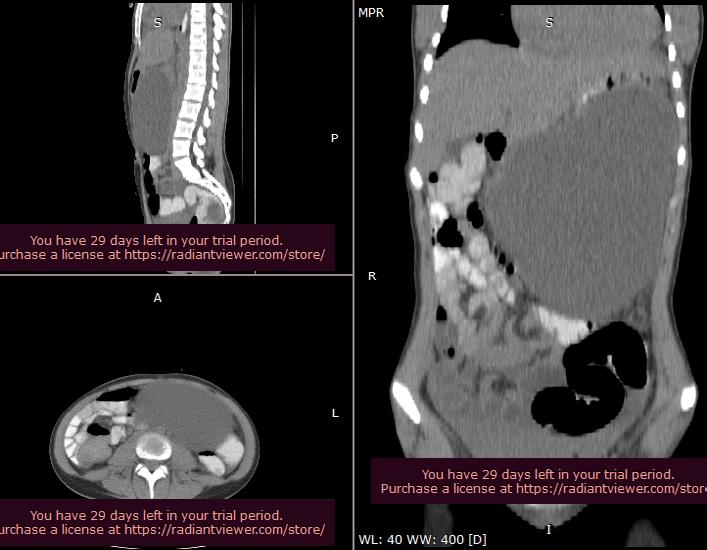

Acalazia în stadiu terminal: provocări de diagnostic pozitiv și diferențial cu hernia hiatală gigantă

Șef Lucr. Dr. Petre Hoară, Prof. Univ. Dr. Silviu Constantinoiu